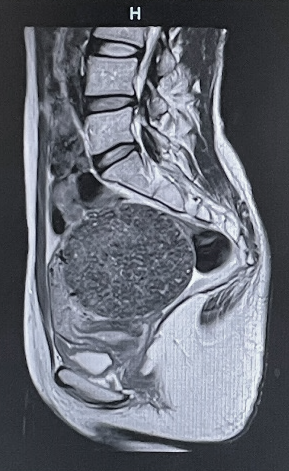

既に定評のある、脳神経、骨関節領域の他に、MRアンギオ(脳血管・四肢血管が描出可能)、MRCP(造影剤を用いない胆管・膵管画像)、急性期脳梗塞の診断(拡散強調像、MRアンギオや灌流画像を組み合わせることで治療方針の決定に有用)などの撮像法にも対応可能です。